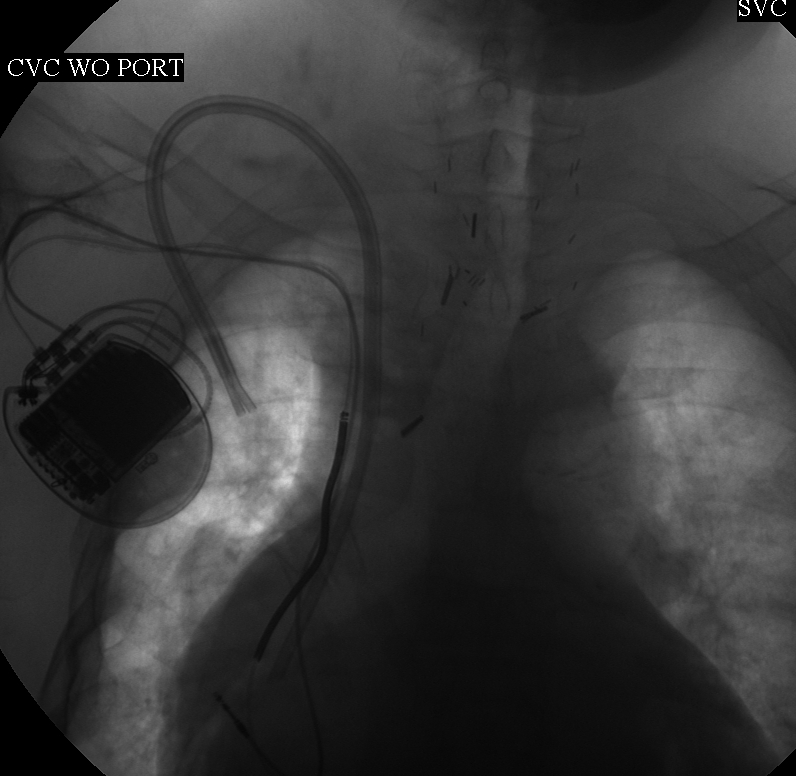

Fluoroscope of the chest after intervention: A double-lumen catheter is tunneled into the right atrium.